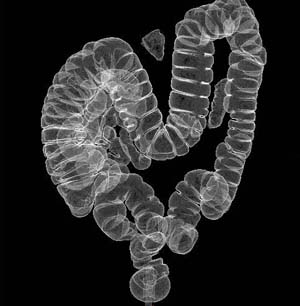

¿µ»óÀÇÇаú´Â ´Ü¼ø X-¼±ÃÔ¿µ, À§ Åõ½Ã°Ë»ç, °æÁ¤¸Æ ½Å¿ìÁ¶¿µ¼ú, Àü»êÈ ´ÜÃþ¿µ»ó ÃÔ¿µ(CT), ÀÚ±â°ø¸í¿µ»ó(MRI), ÃÊÀ½ÆÄ ÃÔ¿µ, Ç÷°ü Á¶¿µ¼ú µî°ú °°Àº ¸ðµç ¿µ»óÁø´ÜÀÇ ÃÔ¿µ ¹× ÆÇµ¶À¸·Î ÀÓ»óÁø´ÜÀ» Çϸç Áø·á¿¡ À¯¿ëÇÑ Á¤º¸¸¦ Á¦°øÇÏ´Â °úÀÔ´Ï´Ù. ºñ¾àÀûÀ¸·Î ¹ßÀüÇÏ´Â ÃÖ÷´Ü ÀǷ῵»ó±â¼úÀ» Àû±ØÀûÀ¸·Î ¼ö¿ëÇÏ¿© µðÁöÅÐ ¿µ»ó ÃÔ¿µ, 3Â÷¿ø ¿µ»ó, CT ȤÀº MRI¸¦ ÅëÇÑ ºñħ½ÀÀû Ç÷°ü Á¶¿µ¼ú µî Ȱ¹ßÇÑ Áø·á ¹× ÀÇ·á ¿¬±¸°¡ ÀÌ·ç¾îÁö°í ÀÖ½À´Ï´Ù.

ÃÖ±Ù¿¡´Â Áø´Ü »Ó ¾Æ´Ï¶ó Ä¡·áÀû ¿ªÇÒÀÇ ºñÁßÀÌ ³ô¾ÆÁö°í ÀÖ½À´Ï´Ù. ¿µ»ó°Ë»ç¿Í µ¿½Ã¿¡ ÃÖ¼ÒÇÑÀÇ Ä§½ÀÀûÀÎ ¹æ¹ýÀ» ÅëÇÑ °£, ½ÅÀå, À¯¹æ µîÀÇ °¢Á¾ °æÇÇÀû »ý°Ë¼ú(Á¶Á÷°Ë»ç)À» ½ÃÇàÇϰí ÀÖ½À´Ï´Ù. ¶ÇÇÑ ³úµ¿¸Æ·ùÀÇ »öÀü¼ú, °£¾ÏÀÇ µ¿¸Æ»öÀü¼ú, °£¾ÏÀÇ ÃÊÀ½ÆÄ»öÀü¼ú, »çÁöµ¿¸Æ°æÈÁõÀÇ ±Ý¼Ó ½ºÅÙÆ® »ðÀÔ¼ú µî ¼ö¼úÀ» ÅëÇÏÁö ¾Ê°íµµ ÃֽŠ¿µ»ó±â±â ¹× ±â¼úÀ» ÀÌ¿ëÇÏ¿© ¸¹Àº ÁúȯÀ» Àϼ±¿¡¼ Ä¡·áÇϰí ÀÖ½À´Ï´Ù.